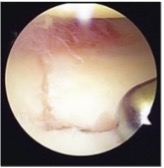

橈骨遠位端骨折に対する鏡視併用手術

橈骨遠位端骨折は頻度の高い骨折の一つで、特に関節内骨折については関節鏡を併用し従来のX線のみでは整復が不十分な関節面の整復を行っています。

鏡視下整復前

整復後